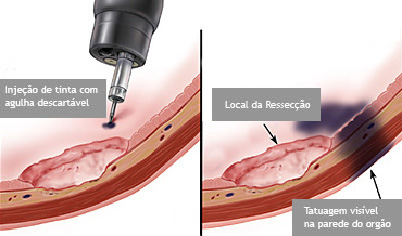

O que é a polipectomia?

A polipectomia é a remoção completa de um pólipo permitindo assim o diagnóstico exato e muitas vezes a cura do próprio problema. Existem várias técnicas para a realização do procedimento que dependem do tamanho e do tipo de pólipo a ser ressecado.

Polipectomia com pinça

Pequenos pólipos podem ser removidos com segurança usando-se apenas uma pinça.

Polipectomia com alça diatérmica

Pólipos maiores necessitam ser removidos com alça e corrente de cauterização. Este procedimento permite cortar a base do pólipo e ao mesmo tempo coagular o local para evitar sangramentos.

Porém alguns pólipos possuem a base (pedículo) largo onde passam vasos calibrosos e por isto tem risco aumentado de sangramento na retirada mesmo usando a corrente de coagulação.

Nestes casos algumas medidas podem ser realizadas para diminuir o risco de sangramento:

Injeção de adrenalina na base do pólipo

Colocação de um laço na base do pólipo para estrangular o pedículo

Alguns pólipos são tão grandes que não podem ser removidos inteiros. Nestes casos o pólipo é retirado em pedaços para poder garantir a sua remoção completa.